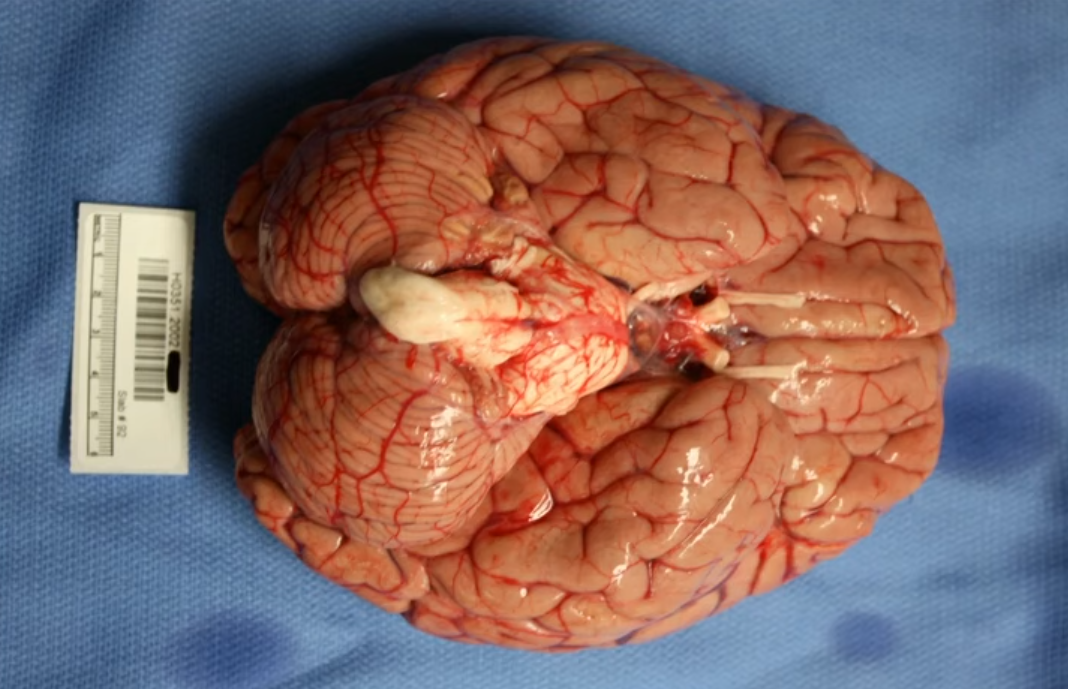

将大脑从颅骨中取出